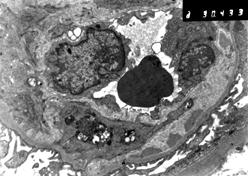

Рис. Мембранопролиферативный гломерулонефрит I типа.

Б. На ЭМ можно различить пять уровней капиллярной стенки, начиная от просвета капилляра: 1) эндотелиальная клетка, 2) новообразованная ГБМ, 3) цитоплазма мезангиальной клетки, 4) первоначальная ГБМ с субэндотелиальными депозитами и 5) подоциты. Стаз мононукларов в просвете капилляра.